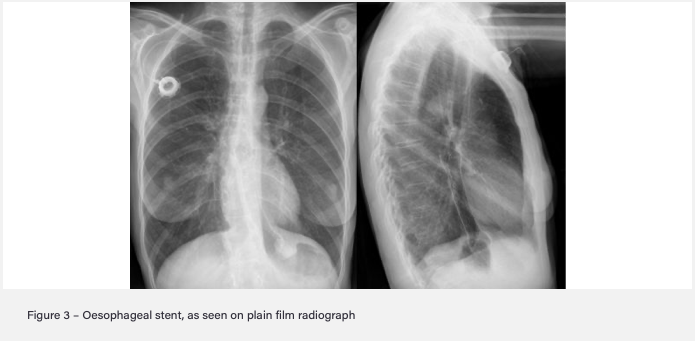

Oesophageal cancer often presents at a late stage so around 70% of patients are treated palliatively. What are some palliative treatment options for this?

- Oesophageal stent if difficulty swallowing